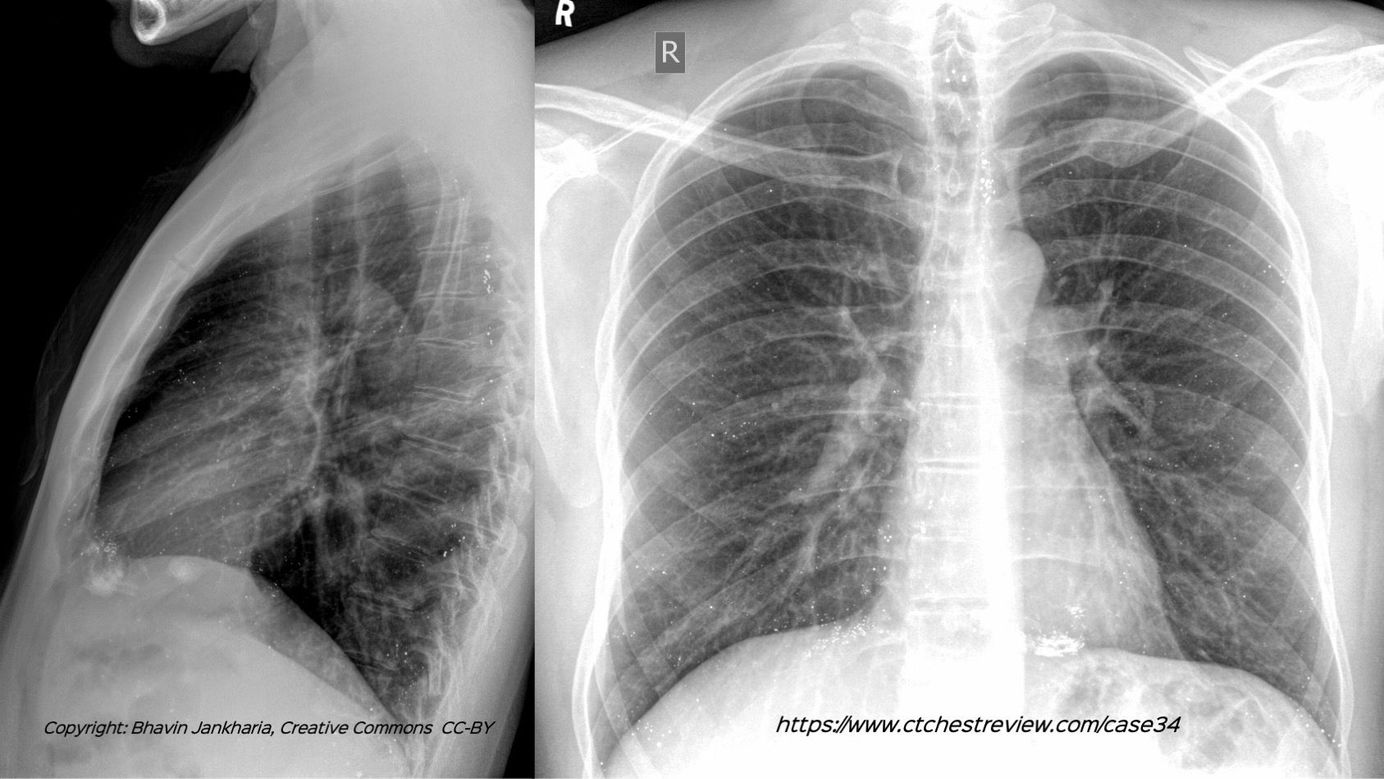

Case 34: All High-Density Foci in the Lungs Are Not Old Calcified Granulomas Members Public

All high-density foci in the lungs are not old calcified granulomas